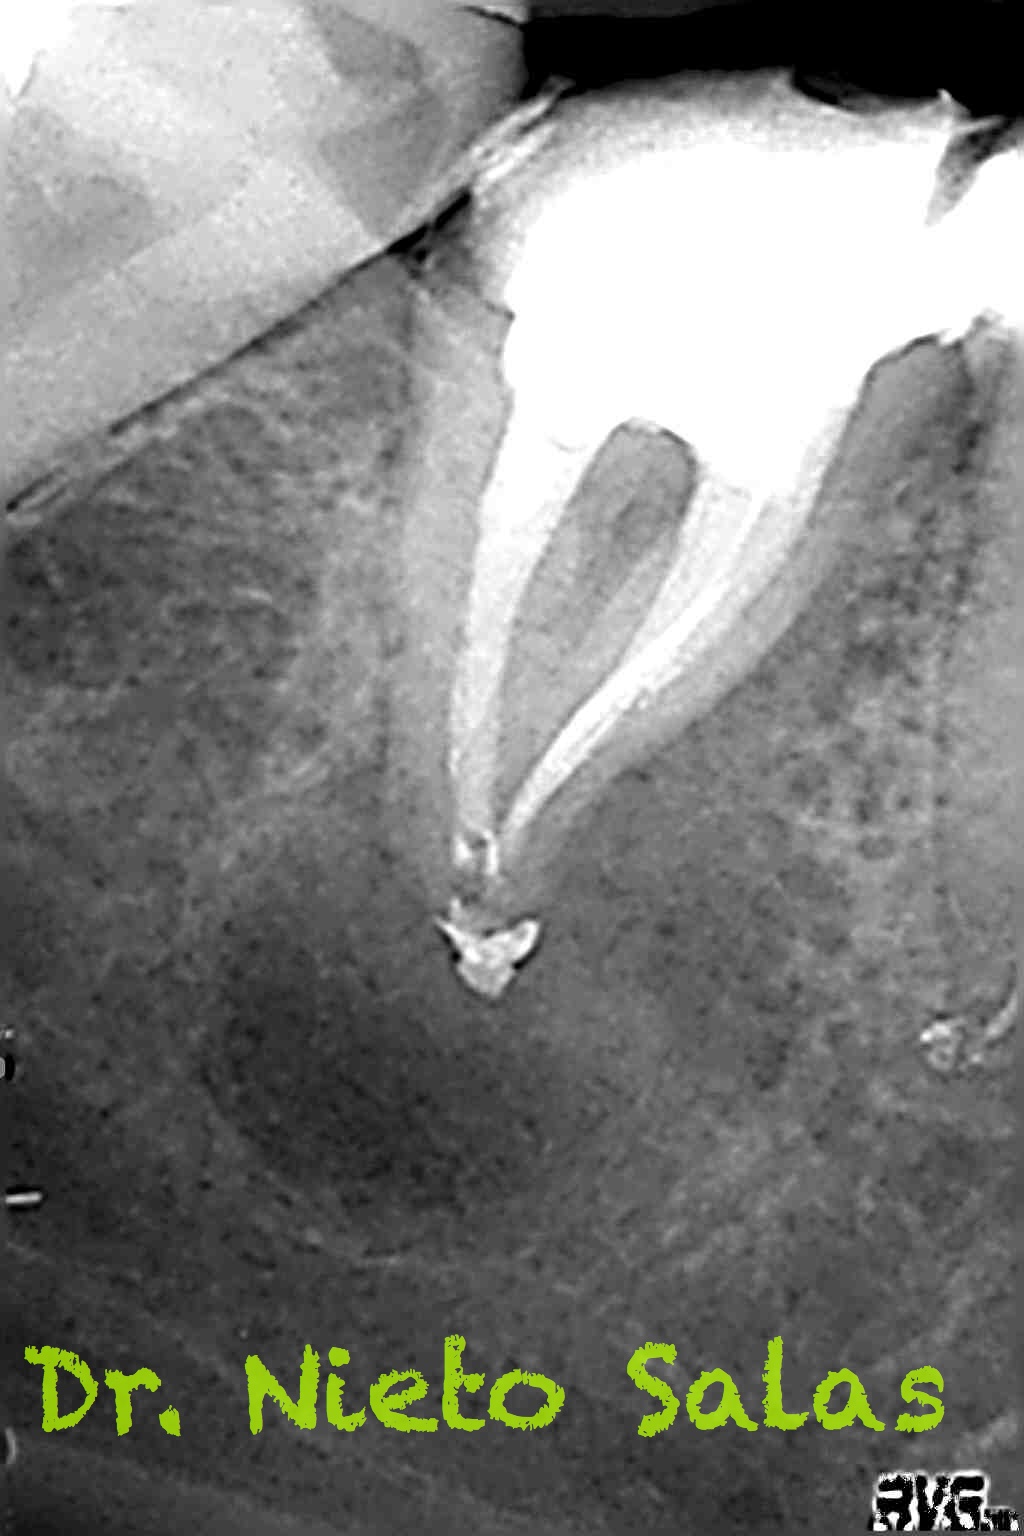

Nos remiten a la clínica a una paciente con un tratamiento previo de endodóncia realizado ya hace unos 5 años y que presenta una agudización del proceso. Se trata de un fracaso endodoncico por una falta de sellado tanto coronal como apical, en el que en el espacio intra-conductos nos encontramos dos léntulos, y en el acceso a los mismos un perno prefabricado.

Los puntos fuertes serán la retirado del perno y de los léntulos, a priori, no muy complicado, pero todo puede cambiar dentro de los conductos. Nuestro objetivo en la primera sesión será llegar a determinar la longitud de trabajo de los diferentes conductos, conformarlos y colocar nuestro Hidróxido de Calcio.

Presentaba un sistema de conductos en el que el conducto distal era acintado y los mesiales podían unirse después de instrumentarlos.

Me gusta ser conservador con los diámetros apicales, para deformarlos lo menos posible. En este caso no fue así por la anatomía que presentaba, adapté bien los conos maestros con un diámetro más o menos 45 en el conducto distal(recuerda que era acintado con lo que no es posible un único cono apical) y 30 los mesiales.